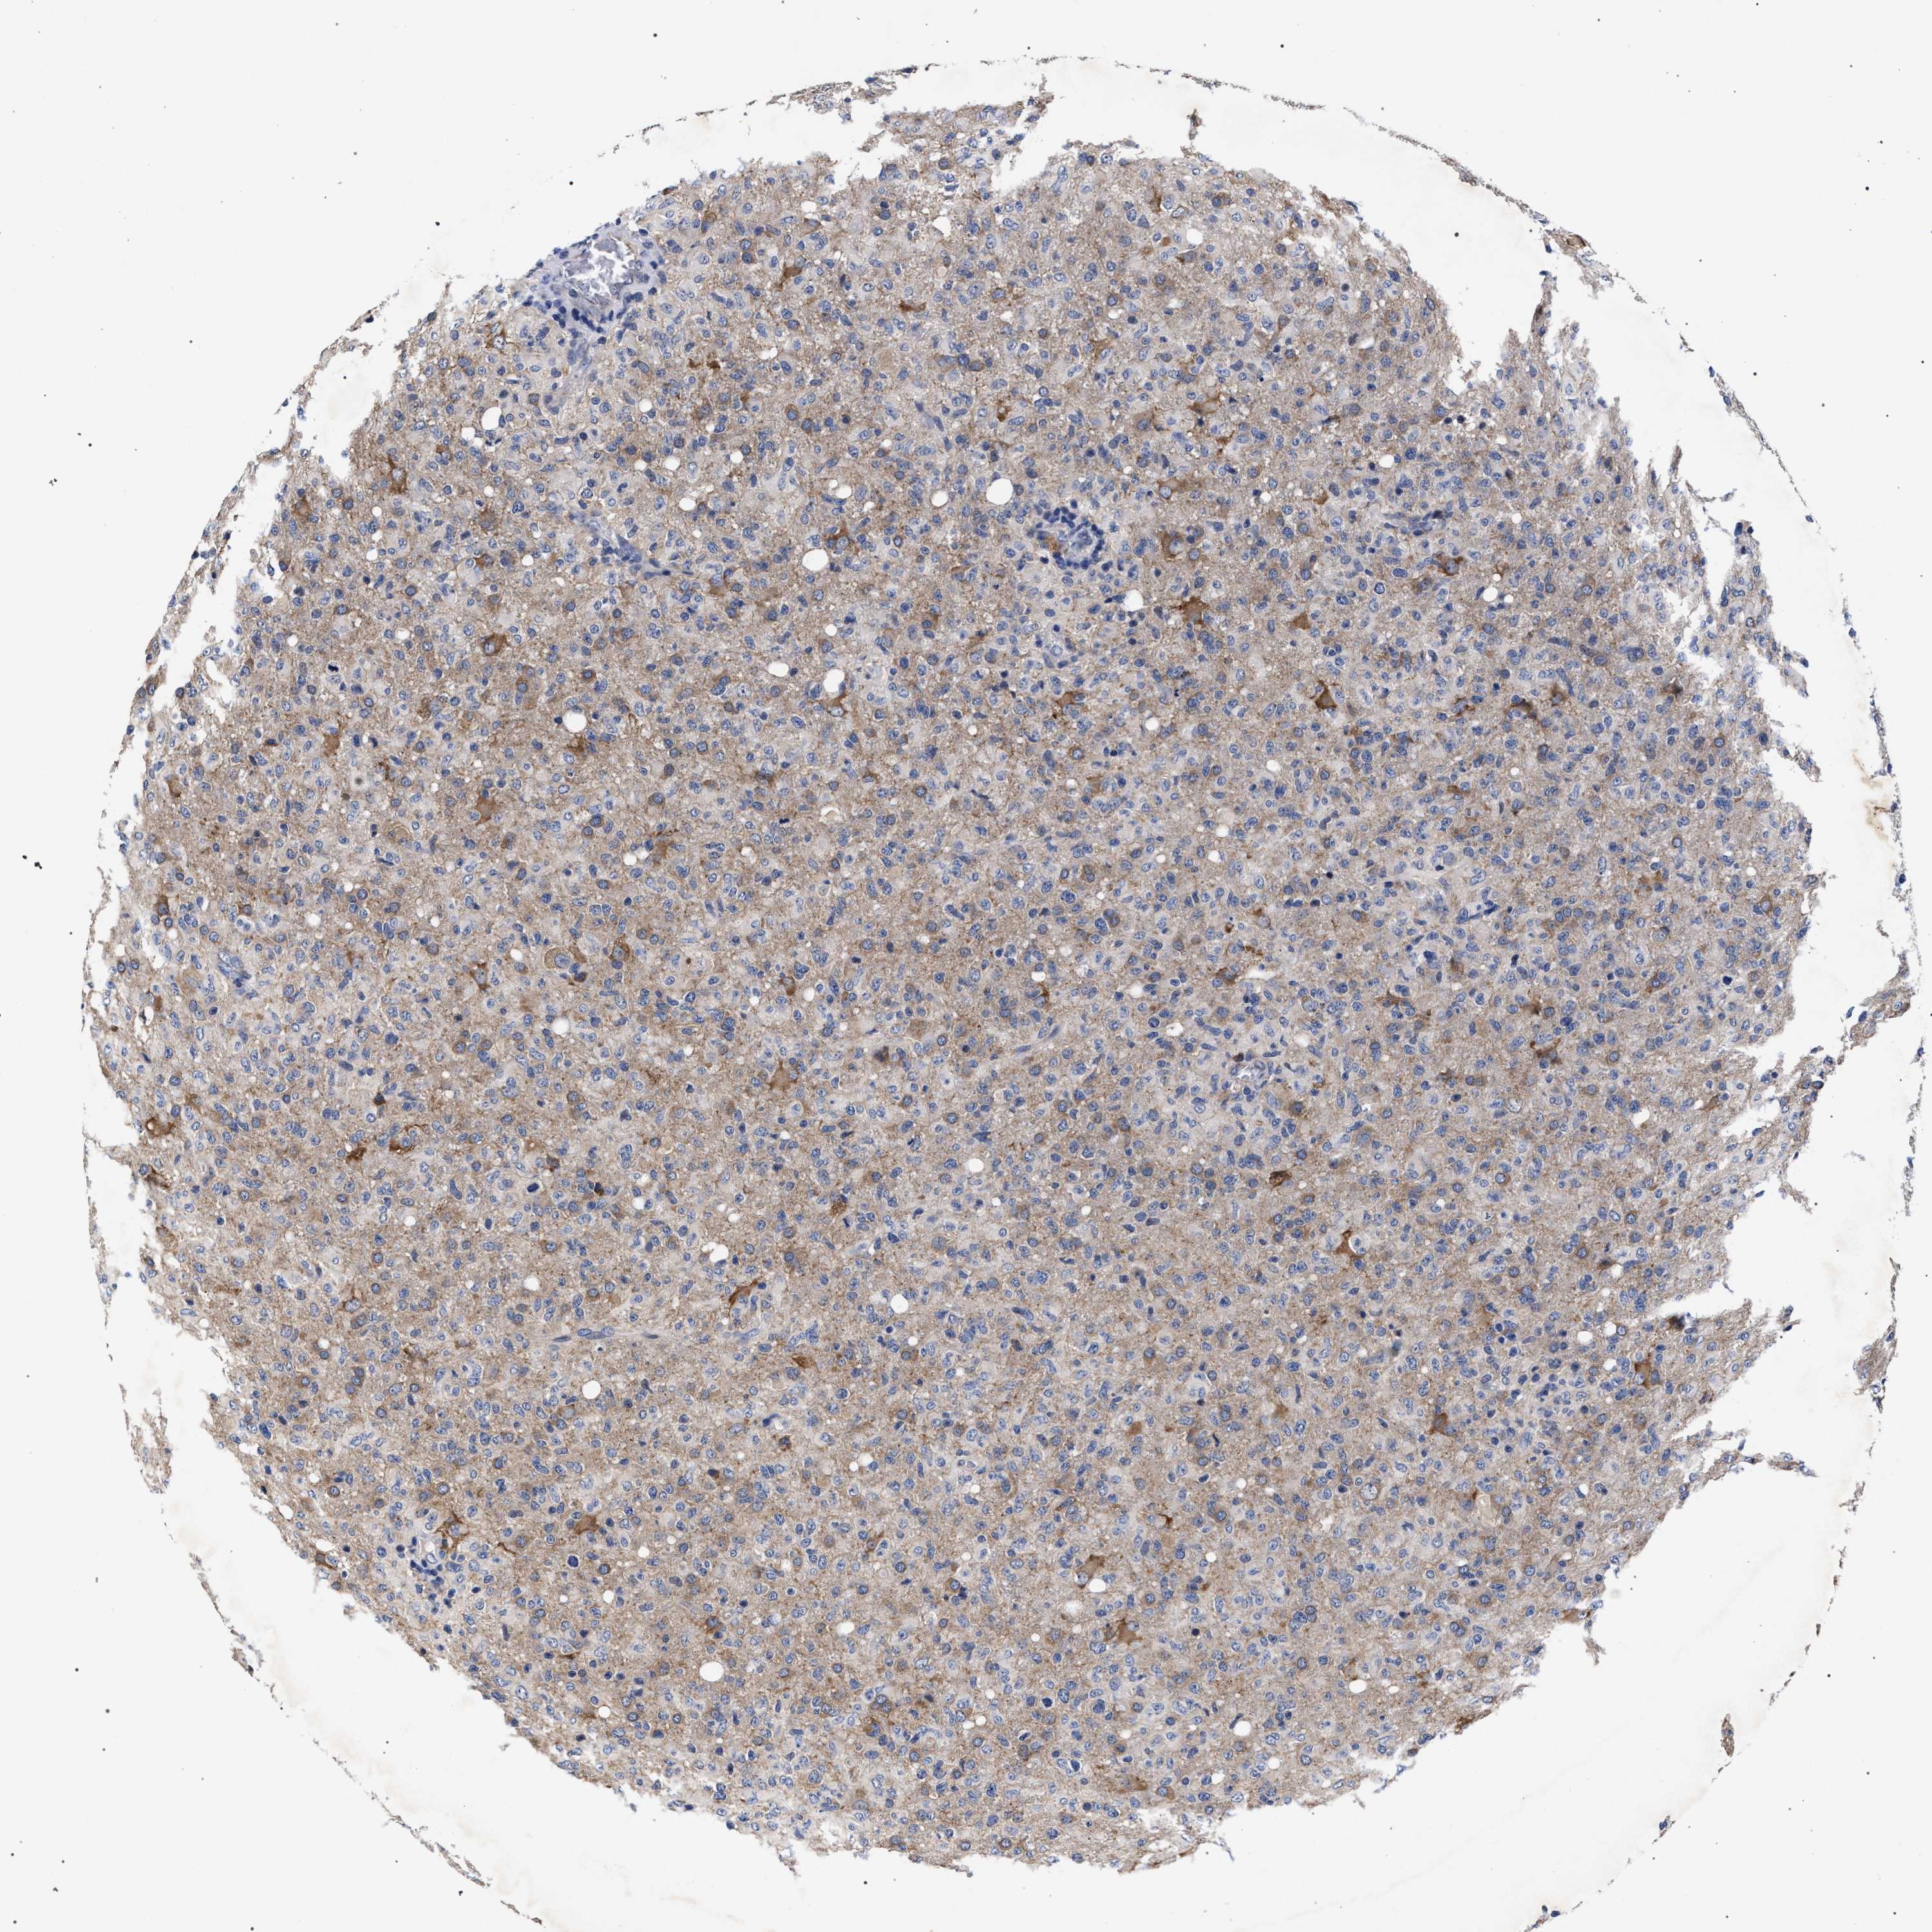

GLIOMA - Protein expressioni

A mouse-over function shows sample information and annotation data. Click on an image to view it in a full screen mode. Samples can be filtered based on level of antibody staining by selecting one or several of the following categories: high, medium, low and not detected. The assay and annotation is described here.

Antibody stainingi

Antibody staining in the annotated cell types in the current human tissue is reported as not detected, low, medium, or high, based on conventional immunohistochemistry profiling in selected tissues. This score is based on the combination of the staining intensity and fraction of stained cells.

Each image is clickable and will lead to virtual microscopy that enables deeper exploration of all samples and also displays staining intensity scores, fraction scores and subcellular localization as well as patient and tissue information for each sample.

Antibody HPA021261

Antibody HPA021325

Staining

High

Medium

Low

Not detected

Intensity

Strong

Moderate

Weak

Negative

Quantity

>75%

75%-25%

<25%

None

Location

Nuclear

Cytoplasmic/membranous

Cytoplasmic/membranous,nuclear

Glioma, malignant, High grade

Glioma, malignant, Low grade